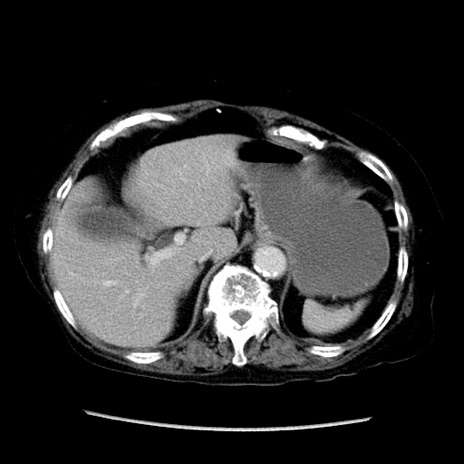

冠状断像